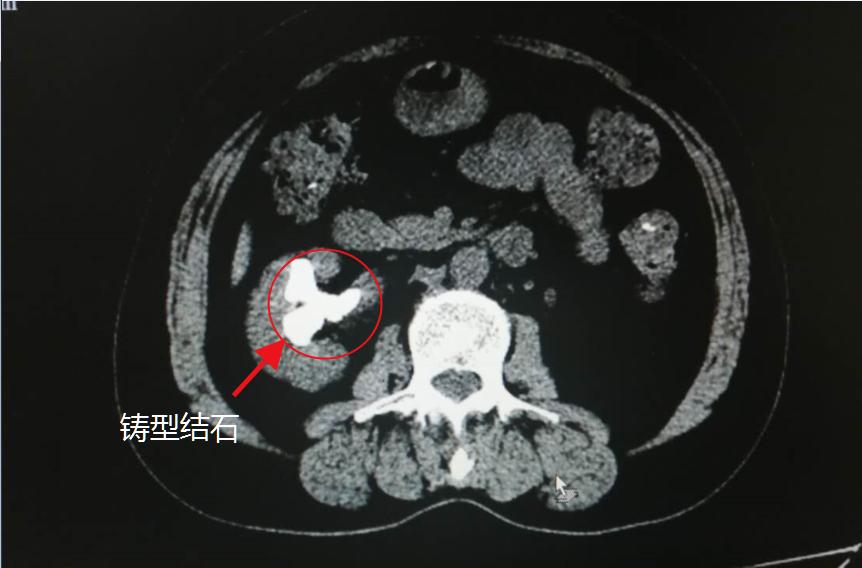

CT检查局部图:左红圈为患者结石

入院CT显示王女士左肾萎缩、右肾铸形结石;另外,尿常规示隐血2+,白细胞3+,证明结石引发尿路感染。